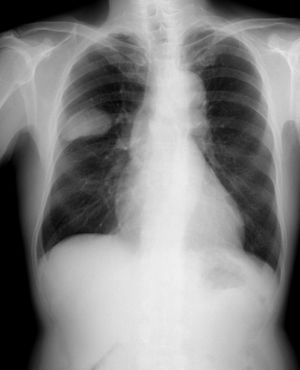

소세포암종은 주로 폐에서 발생하는 악성 종양으로, 폐암의 한 종류이다. 소세포암종은 폐암 중에서도 예후가 좋지 않으며, 림프절 침투와 원격 전이가 빠르게 진행된다. 종류로는 소세포 폐암, 혼합 소세포 폐암, 폐외 소세포암 등이 있다. 흡연은 주요 위험 요인이며, 흉부 X선, CT, 조직 검사 등을 통해 진단한다. 치료는 화학 요법, 방사선 치료, 면역 치료 등이 사용되며, 재발 시에는 다른 치료법을 시도한다. 5년 생존율은 낮지만, 최근 면역 치료 등의 발전으로 치료 성과가 개선되고 있다.

5. 진단